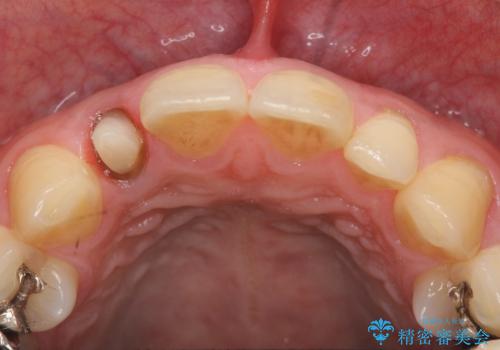

- 金属を使っていない被せ物に替えたいといらっしゃった方の症例です。

再根管治療終了後、オールセラミッククラウンによる補綴を行いました。